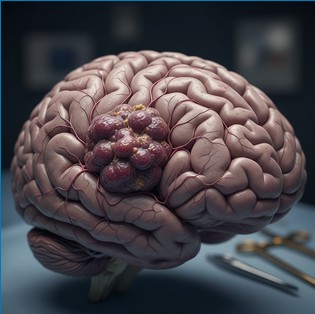

O tumor cerebral é uma condição que desperta muitas dúvidas e preocupações. Embora seja relativamente raro quando comparado a outros tipos de câncer, ele pode afetar pessoas de qualquer idade e apresentar diferentes níveis de gravidade. Entender os sintomas de tumor cerebral, os tipos de tumor cerebral e as opções de tratamento de tumor cerebral…

Conheça os principais métodos e exames para o diagnóstico preciso de tumores cerebrais em adultos na prática clínica.